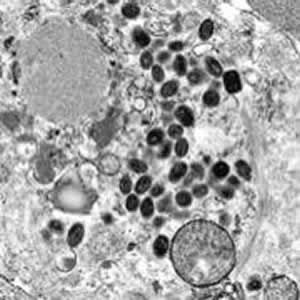

Гистоплазмоз относится к числу глубоких, системных микозов и вызывается диморфным грибом Нiastoplasma capsulatum.

Заражение происходит аэрогенно, при вдыхании спор гриба. Особенно их много в почве, загрязненной испражнения птиц и летучих мышей. Попадая в альвеолы, споры превращаются в дрожжеподобные клетки. Затем инфекция распространяется во все внутренние органы. Очаги поражения подвергаются казеозному некрозу с последующим обызвествлением, напоминая очаги Гона. Возбудитель обладает свойством паразитировать внутри клеток ретикулоэнлотелиальной системы, поэтому гистоплазмоз называют иногда ретикулоэндотелиальным циотмикозом.

Окончательный диагноз может быть поставлен на основании обнаружения возбудителя или дрожжевых клеток при посеве материала о больного (мокрота, кал), или в гистологических препаратах печени лимфатических узлов, костного мозга.